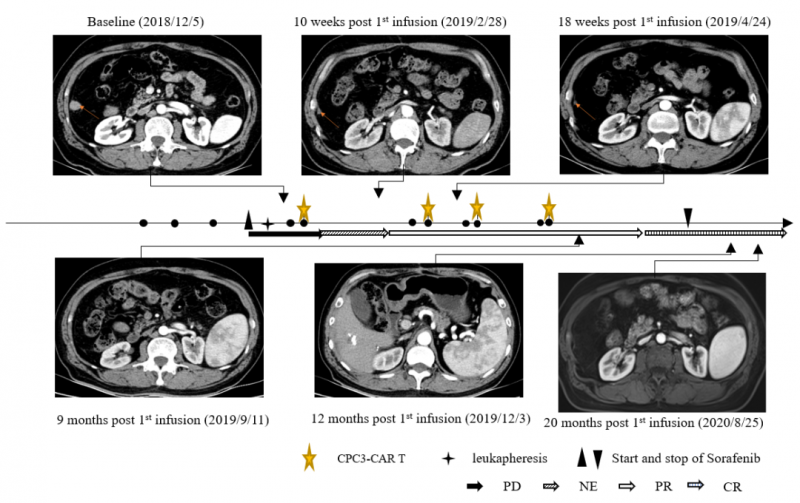

这是一名患有乙型肝炎病毒(HBV)相关肝细胞癌的60岁男性,于2018年5月接受手术,2018年8月术后发生肝癌复发并出现肺转移,随后又进行了经动脉化疗栓塞治疗(TACE)处理肝部病灶和介入消融处理肺部转移。不幸的是,在2018年11月6日出现疾病进展,有幸符合临床试验入组条件。在入组后,该名患者接受单采制备GPC3 CAR-T细胞。在单采后7天,患者开始服用索拉非尼,400mg/次,2次/d。患者接受了4个周期的GPC3 CAR-T细胞(CT011)治疗,每个周期分为两次输注。在接受CT011治疗的每个周期之前,进行清淋化疗预处理。共输注4×109 个GPC3 CAR-T细胞。

CT011联合索拉非尼治疗耐受性良好。患者从第3个月开始达到部分缓解(PR),并在第一个 CT011 输注周期后的第12个月达到完全缓解。肿瘤超过36个月没有进展,在第一次输注后保持完全缓解状态超过24个月。